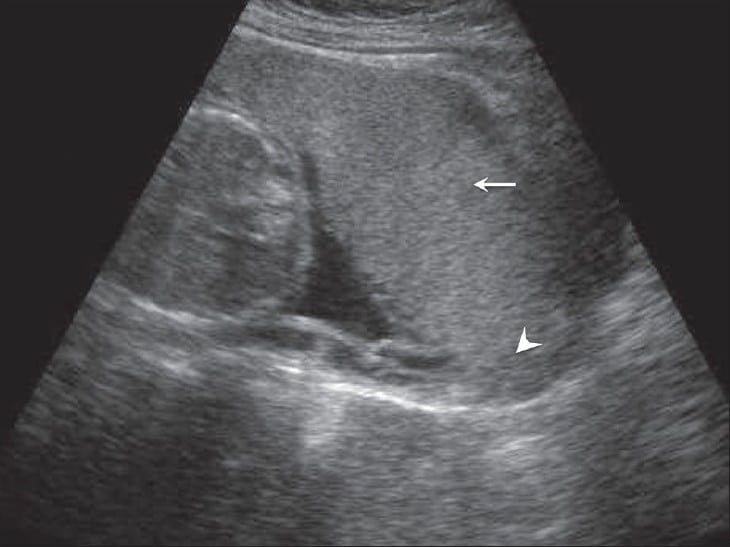

Placenta Praevia - Podcast Version TeachMeObGyn 0:00 / 0:00 1x 0.25x 0.5x 0.75x 1x 1.25x 1.5x 1.75x 2x Placenta praevia is where the placenta is fully or partially attached to the lower uterine segment. It is an important cause of antepartum haemorrhage – vaginal bleeding from week 24 of gestation until delivery. In this article, we shall look at the pathophysiology, clinical features and management of placenta praevia. Pathophysiology Placenta praevia is where the placenta is fully or partially attached to the lower uterine segment. There are two main types: Minor placenta praevia – placenta is low but does not cover the internal cervical os. Major placenta praevia – placenta lies over the internal cervical os. A low-lying placenta is more susceptible to haemorrhage, possibly due to a defective attachment to the uterine wall. Bleeding can be spontaneous, or provoked by mild trauma (e.g vaginal examination). Additionally, the placenta may be damaged as the presenting part of the fetus moves into the lower uterine segment in preparation for labour. By Blausen.com staff [CC BY 3.0], via Wikimedia Commons Fig 1Placenta praevia is where the placenta is attached to the lower uterine segment. Risk Factors The main risk factor for placenta praevia is previous caesarean section. There is a 1 in 160 incidence associated with 1 previous section – this rises to 1 in 60 with 2 previous sections, to 1 in 10 with 4 sections. The other risk factors include: High parity Maternal age >40 years Multiple pregnancy Previous placenta praevia History of uterine infection (endometritis) Curettage to the endometrium after miscarriage or termination Clinical Features Any woman presenting with antepartum haemorrhage (APH) should be assessed in a systematic manner (see box below). Placenta praevia classically presents as painless vaginal bleeding, this can vary between spotting to massive haemorrhage. There can be pain if the woman is in labour. Examination may reveal risk factors pertinent to placenta praevia – e.g. c-section scar or multiple pregnancy. The uterus is usually not tender on palpation. Assessment of Antepartum Haemorrhage History The following questions are useful to ask in the assessment of antepartum haemorrhage: How much bleeding was there and when did is start? Was it fresh red or old brown blood, or was it mixed with mucus? Could the waters have broken (membranes ruptured?) Was it provoked (post-coital) or not? Is there any abdominal pain? Are the fetal movements normal? Are there any risk factors for abruption? e.g. smoking/drug use/trauma – domestic violence is an important cause. If the bleed is ongoing, or if there has been a significant vaginal bleed, ABC assessment and resuscitation is vital. If the woman is clinically stable, proceed to examination. General Examination On general examination, the following should be assessed: Pallor, distress, check capillary refill, are peripheries cool? Is the abdomen tender? Does the uterus feel ‘woody’ or ‘tense’ (which may indicate placental abruption)? Are there palpable contractions? Check the lie and presentation of the fetus/fetuses. Ultrasound can be used to help. Check fetal wellbeing with a cardiotocograph (CTG) at 26 weeks gestation or above: (otherwise auscultate the fetal heart only). Read the hand-held pregnancy notes: are there scan reports? This will be helpful in establishing whether there could be placenta praevia Assessment of Bleeding Lastly, the bleeding itself should be assessed: Externally e.g. by looking at pads. Cusco speculum examination: avoid this until placenta praevia has been excluded by USS. Look for whether blood is fresh red or dark. How much blood is there? Are there clots? Are there any cervical lesions? Is there any cervical dilatation, or any chance that the membranes have ruptured? Take triple genital swabs to exclude infection if the bleeding is minimal Digital vaginal examination: A digital vaginal examination with known placenta praevia should NOT be performed as it could cause massive bleeding. In minor bleed, when placenta praevia is excluded, it can help to establish whether the cervix is beginning to dilate. Avoid digital VE if the membranes have ruptured. Differential Diagnoses Placenta praevia is an important cause of antenatal haemorrhage; but it is not the most common. Differential diagnoses to consider include: Placental abruption – where a part or all of the placenta separates from the wall of the uterus prematurely. Vasa praevia – where fetal blood vessels run near the internal cervical os. It is characterised by a triad of (i) Vaginal bleeding; (ii) Rupture of membranes; and (iii) Fetal compromise. The bleeding occurs following membrane rupture when there is rupture of the umbilical cord vessels, leading to loss of fetal blood and rapid deterioration in fetal condition. Uterine rupture – a full-thickness disruption of the uterine muscle and overlying serosa. This usually occurs in labour with a history of previous caesarean section or previous uterine surgery such as myomectomy. Local genital causes: Benign or malignant lesions – e.g. polyps, carcinoma. cervical ectropion (common). Infections – e.g. candida, bacterial vaginosis and chlamydia. By Gynpath.ru [CC BY-SA 4.0], via Wikimedia Commons Fig 2Cervical ectropion on speculum examination. This is a common cause of antepartum haemorrhage. Investigations If major bleeding is suspected, resuscitate and perform investigations simultaneously. Haematology Full blood count – assess any maternal anaemia. Clotting profile Kleihauer test – if the woman is Rhesus negative (to determine the amount of feto-maternal haemorrhage and thus the dose of Anti-D required). Group and Save – if blood group is unknown. Cross-match – if the clinical presentation is likely to warrant transfusion. Biochemistry These are performed to exclude hypertensive disorders including pre-eclampsia and HELLP syndrome, and any other organ dysfunction: Urea and electrolytes Liver function tests Assess Fetal Wellbeing In women above 26 weeks gestation, a cardiotocograph (CTG) should be performed to assess fetal wellbeing. Imaging The definitive diagnosis of placenta praevia is via ultrasound. There is a short distance between the lower edge of the placenta and internal os. Indian Journal of Radiology and Imaging [CC BY 4.0] Fig 3Anterior placenta previa. The placenta (arrow) has covered the internal os completely (arrowhead). Management Any woman presenting with a significant antepartum haemorrhage should be resuscitated using an ABCDE approach. Do not delay maternal resuscitation in order to determine fetal viability. Placenta praevia may be identified in an asymptomatic patient at their 20-week ultrasound scan: Placenta praevia minor – a repeat scan at 36 weeks is recommended, as the placenta is likely to have moved superiorly. Placenta praevia major – a repeat scan at 32 weeks is recommended, and a plan for delivery should be made at this time. In cases of confirmed placenta praevia, Caesarean section is the safest mode of delivery. Placenta praevia major usually warrants an elective Caesarean section at 38 weeks. In all cases of antepartum haemorrhage, give anti-D within 72 hours of the onset of bleeding if the woman is rhesus D negative. Rate This Article